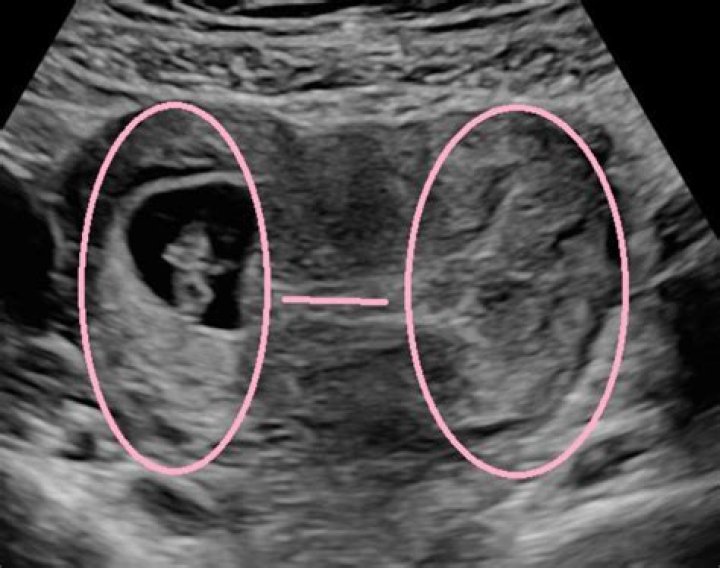

Is it harder to see an embryo with a tilted uterus?

You could also have a tilted uterus, which can make it harder to see your baby until they’re a little bigger. That said, the 7-week ultrasound could also reveal a hard truth about the health of your pregnancy.